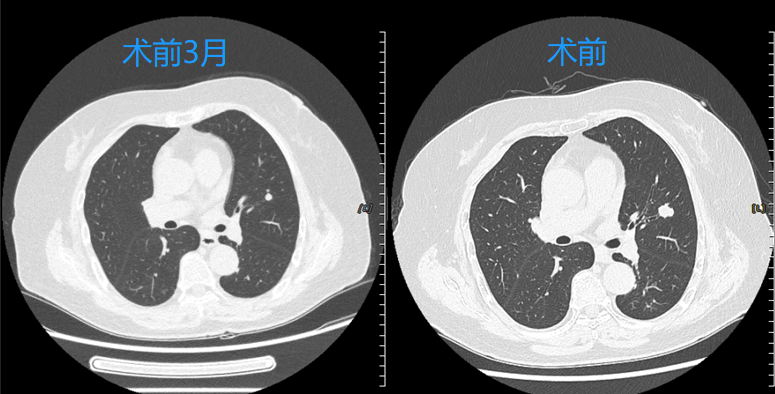

患者为女性,70岁,确诊气管腺样囊性癌两年并出现双肺多发转移瘤,其中一个病灶在近3个月随访中出现快速生长,患者和家属要求积极治疗,控制肿瘤生长及转移速度。考虑到腺样囊性癌对于传统放化疗等治疗不敏感,经多学科团队(MDT)综合评估后,呼吸与危重症医学科介入团队决定采用国际前沿的经支气管镜冷冻消融术,精准消融肿瘤病灶,最大限度保护正常肺组织。

快速康复:患者术后当日即可下床活动,术后24小时复查胸部CT,冷冻消融区域覆盖结节病灶,3天后顺利出院,生活质量不受影响。